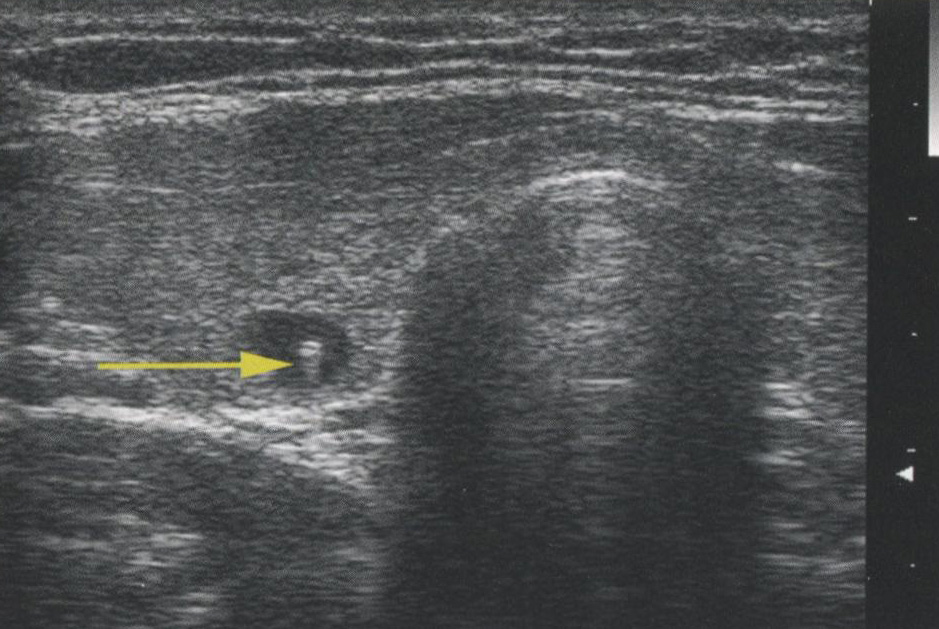

Артефакт «хвост кометы» — другая весьма частая находка, появляющаяся из-за реверберации (рис. 2.19, 2.20). Коллоидные узлы могут содержать тонкие кристаллы, образовавшиеся из-за высыхания желатиноподобного коллоидного вещества. Отражение звуковых волн от такого кристалла приводит к возникновению яркого пятна. Однако, в отличие от кальцификации мягких тканей, кристаллы начинают вибрировать под влиянием УЗ-энергии. Вибрация создает звуковые волны, которые возвращаются на датчик после первично отраженного сигнала. Также называемые артефактами «дребезжания сигнала» (ringdown), «кошачий глаз» (cats eye) (рис. 2.21) или «стремянка» (stepladder), эти «хвосты комет» помогают отличить обычно доброкачественные уплотнения в коллоидных узлах от очень подозрительных микрокальцификатов. Несмотря на то что артефакты «хвост кометы» чаще всего появляются в доброкачественных коллоидных узлах, они могут также выявляться в разрешающихся гематомах, а в редких случаях описаны при ПРЩЖ.

Рис. 2.20. «Хвост кометы». Еще один пример артефакта «хвост кометы» в доброкачественном коллоидном узле